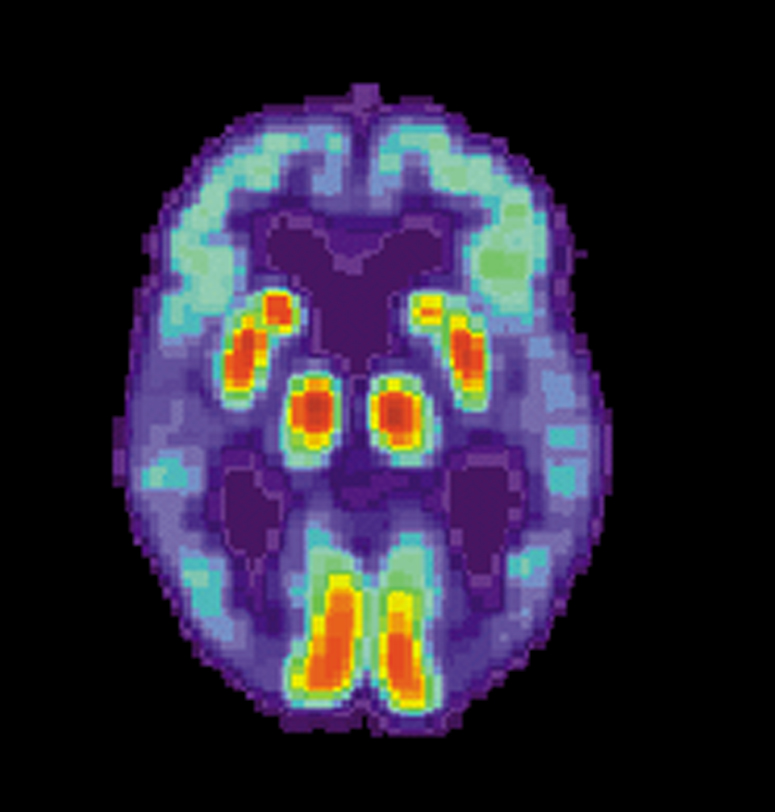

Диагностика обычно включает серию оценок, куда входят тесты на память и способность к познанию. Пациента проводят через серию тестов, чтобы выяснить, не вызваны ли проблемы с памятью другими причинами: физическим недомоганием или приемом лекарств. Есть и другие виды слабоумия, не имеющие отношения к болезни Альцгеймера. Также сканируют мозг и делают поясничные пункции, чтобы определить концентрацию амилоида — протеина, который является критерием наличия недуга.

Последние исследования показали, что этот протеин начинает накапливаться за 20 лет до появления симптомов грозной болезни в виде усиливающегося слабоумия. Развитие сканирующей техники, выявляющей амилоид на ранней стадии, позволяет выявлять будущих пациентов, включая тех, кто даже не подозревает, что его ждет.